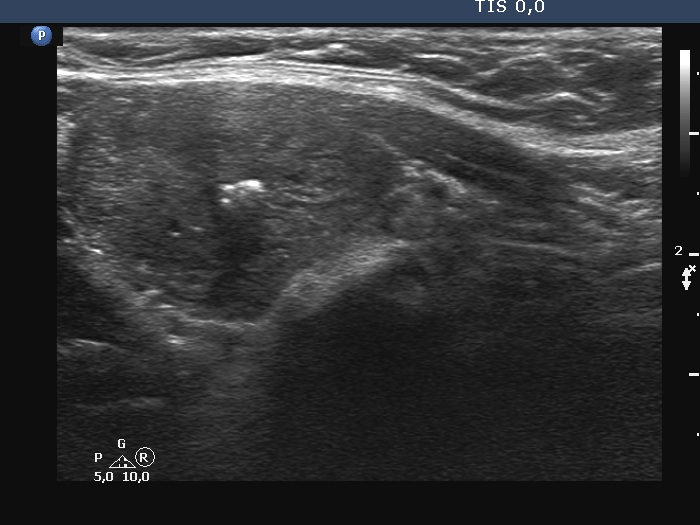

Ultrasonography. The right lobe was substantially enlarged and hypoechoic. It had macrocalcifications. The issue was whether the lobe was composed of a large nodule or only diffuse enlargement was present. The left lobe was much smaller. This lobe was also hypoechoic but to a lesser extent as was the right lobe. The vascularity was increased in the right while decreased in the left lobe.

The issue was whether the lobe was composed of a large nodule or only diffuse enlargement was present. On some still images, it seemed evident that there was a nodule. But we should never forget, that the reality is much more represented by videos. When we stop the continuous scan significantly affects what we see in a still image, which can therefore very easily be misleading. In the video, I highlighted those features on which we could decide considering only the ultrasound presentation that this very likely a nodule.